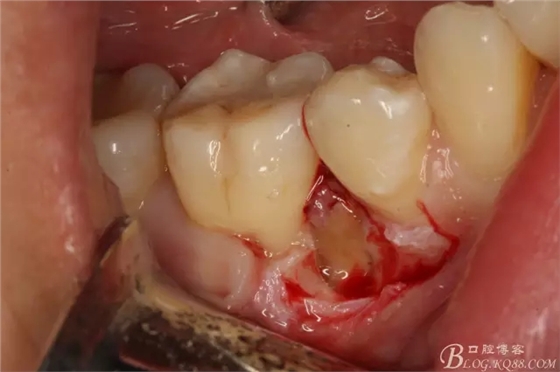

圖8.高速球鉆去骨約3mm.

圖9.暴露45頰側(cè)根面約1/2.牙根與44、46牙根緊緊相鄰。無(wú)法直接用挺。

圖10.高速裂鉆垂直分根

圖11.形成牙根中央一個(gè)約5mm長(zhǎng)、2mm寬溝槽。